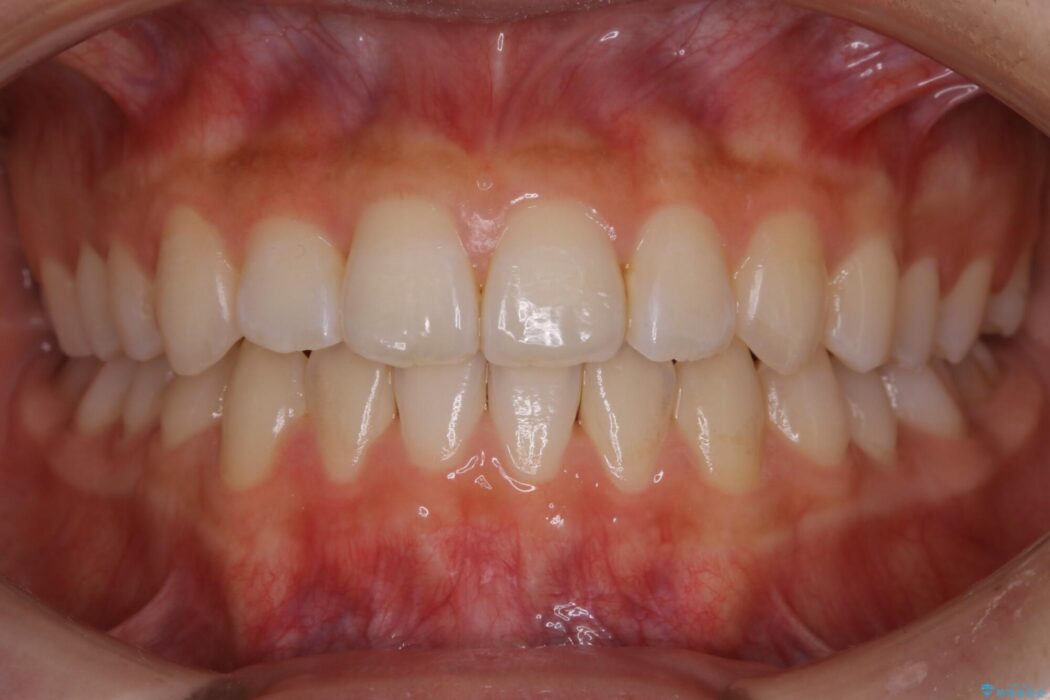

治療後について

正常な噛み合わせ位置へと改善したことにより奥歯で噛みしめることができ、加えて見た目も受け口から変わって大変ご満足いただけました。